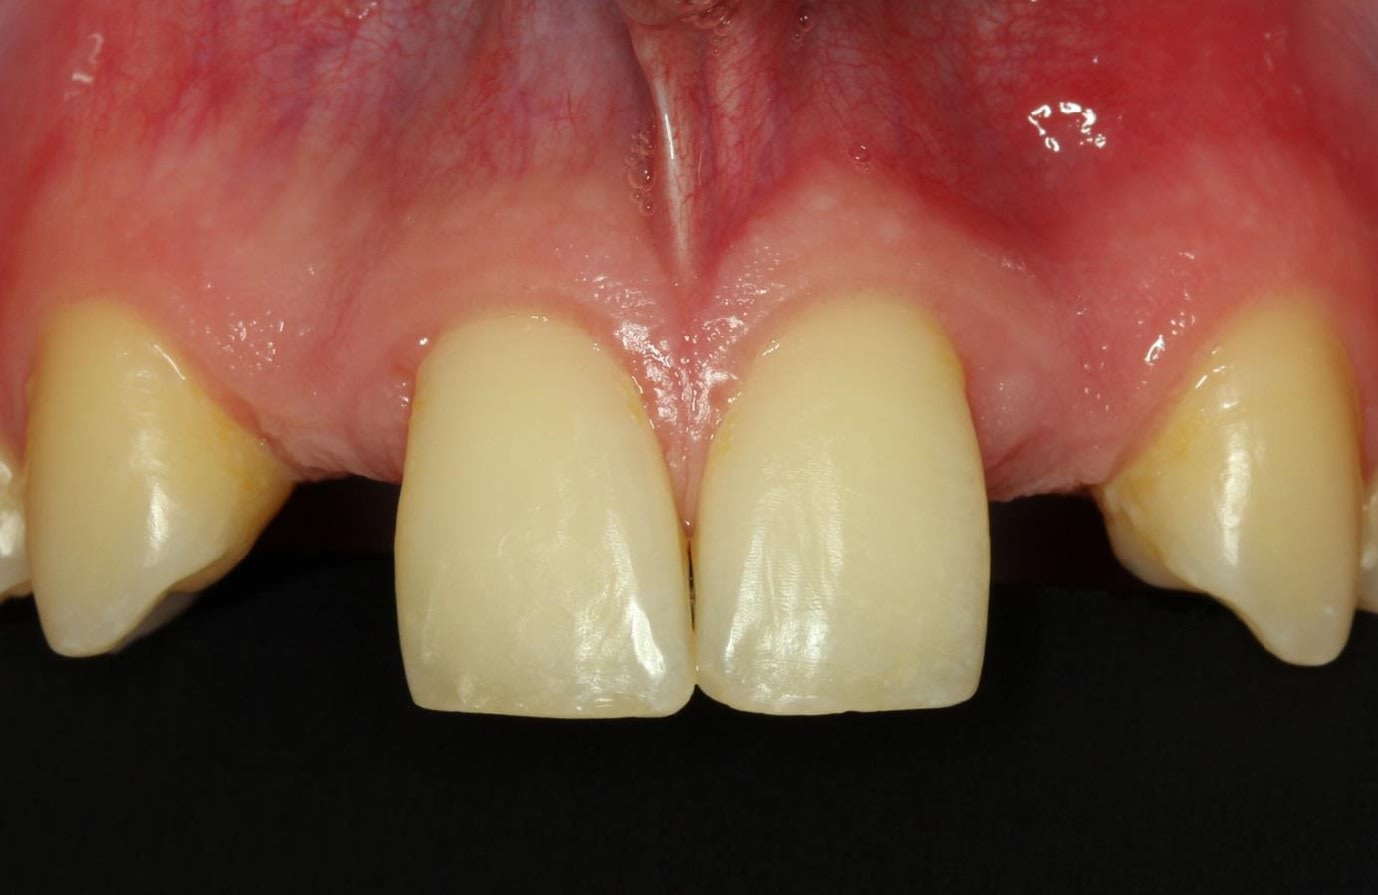

Both the patient and practitioner were satisfied with the extraoral and intraoral appearance after treatment. This was manifested by superb gingival development and good pink/white esthetics (Figure 20 and Figure 21). Despite the initial very limited gap widths and the unfavorable interradicular space conditions, the final result was excellent.